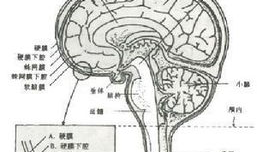

脑膜刺激征检查视频,直观解析临床诊断技巧

你有没有想过,去医院看病的时候,医生有时候会给你来点“特殊待遇”?比如说,给你做个脑膜刺激征检查。这听起来是不是有点陌生?别急,...